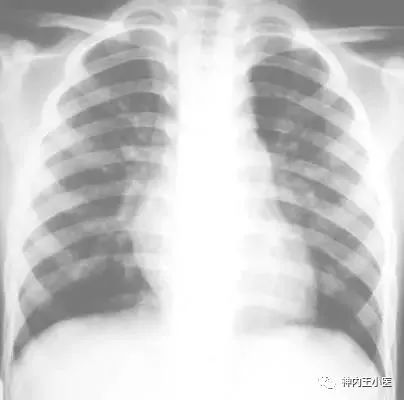

正常肺片x光图片,正常肺部CT

肺部正常的x光片图片

正常人的肺部x光图片

正常肺部x光片

正常健康肺的x光图片

正常人肺部x光片

健康的肺x光图片

正常x光胸片

健康人的肺部x光图片